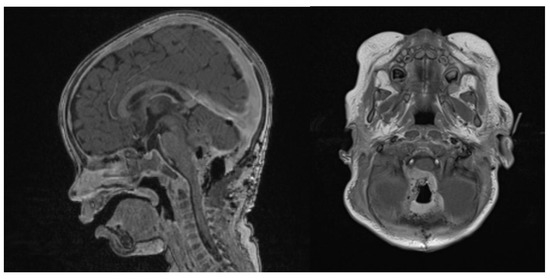

At the last follow-up at 23 months old, the patient did not show any sign of recurrence, with stable enhancing tissue on the floor of the IVth ventricle. Clinical examination was normal, as was global development (as stated by a consultant infantile neuropsychiatrist) (Figure 7). No adverse or unanticipated events were assessed. In this particular situation, local proton therapy (according to the ACNS0333 trial) was recommended [24].

Figure 7.

14 months post-operative gadolinium T1 sagittal and axial sequences, showing no signs of recurrence.